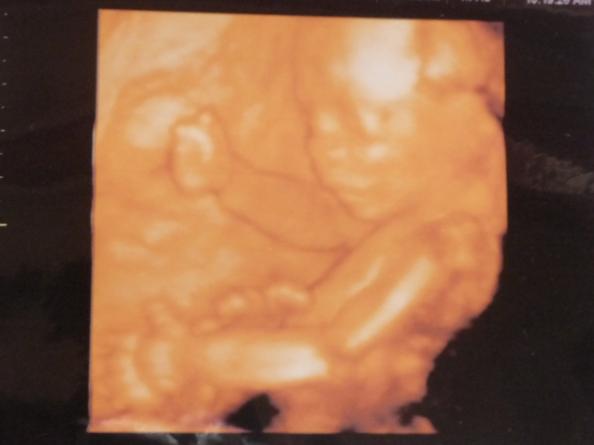

tappancsos